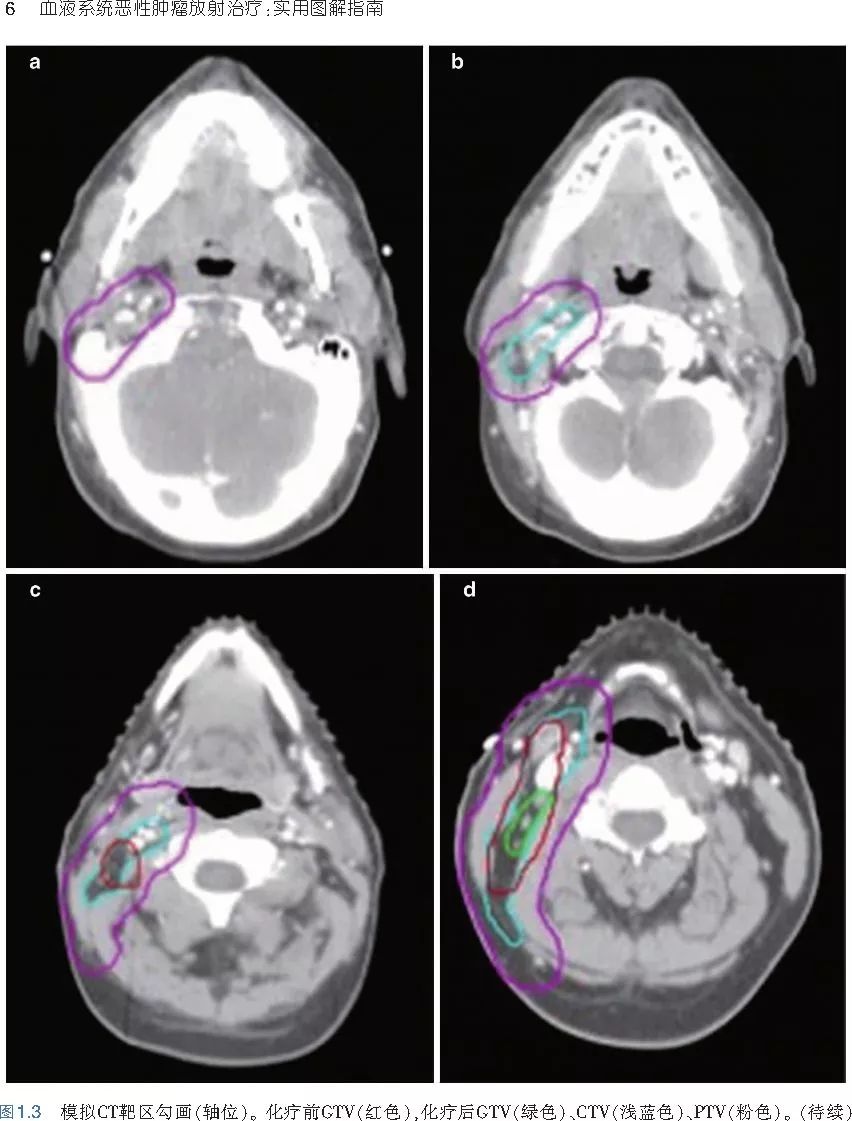

❤ 展开疾病诊断、病理描述及治疗方向的详细阐述,包含医学影像,图文并茂,深入浅出。

本书案例讨论遵循标准格式,包括临床描述,其次是与诊断相关的病理描述和分期,然后详细讨论治疗选择。最后,确定治疗方案,并提供所使用的规划放疗技术/方式的图像。对放射肿瘤医生进行临床决策非常有帮助,对于血液病临床医生也有很好的指导作用。